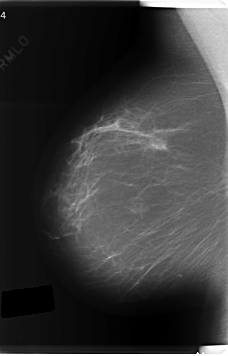

C_0219_1.RIGHT_MLO

RIGHT_MLO LINES 6040 PIXELS_PER_LINE 3864 BITS_PER_PIXEL 12 RESOLUTION 50 NON_OVERLAY